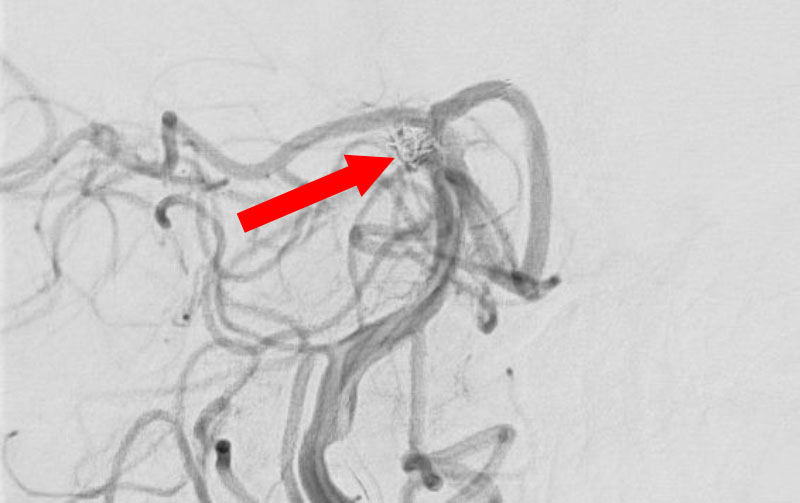

くも膜下出血

左中大脳動脈瘤破裂

40代

救急外来

No.1596 手術後